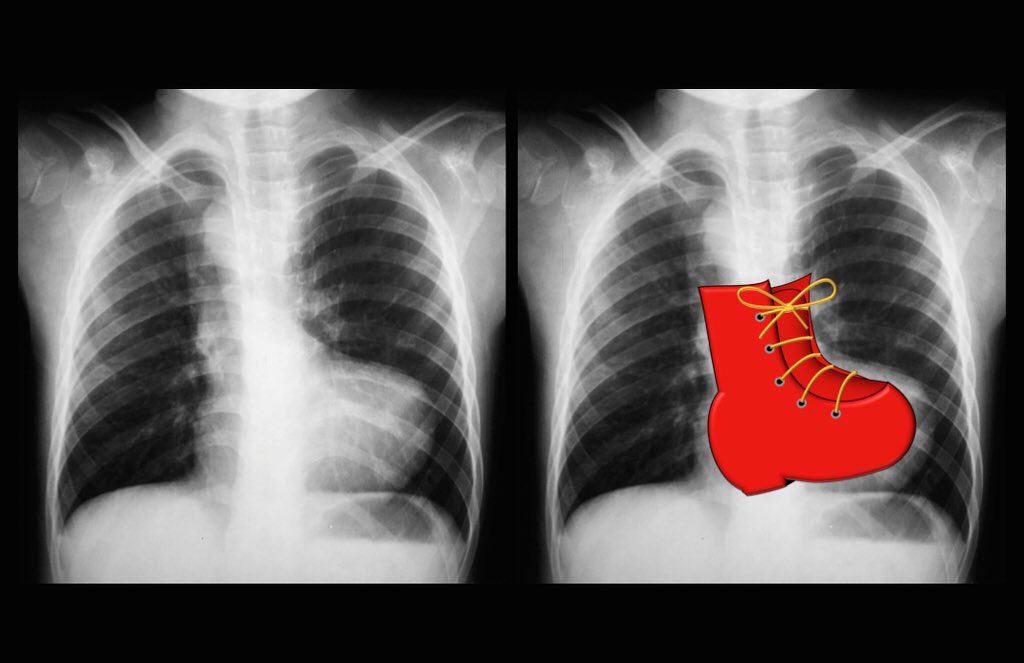

A frontal chest radiograph classically shows cardiomegaly with cardiac contours classically described as appearing like an egg on string 1. Parallel in d loop transposition.

Figure of 8 snowman condition. Egg on a string sign also referred to as egg on its side refers to the cardiomediastinal silhouette seen in transposition of the great arteries tga. In cases with greater degrees of cardiomegaly the term egg on a side has been used.

The appearance of the enlarged heart at chest radiography also has been likened to the profile of an egg on its side 13. Basics of chest x ray part 5 the hilum and mediastinum. Scribed as an egg on a string fig 1the right atrial border is abnormally convex and the left atrium commonly is enlarged because of in creased pulmonary blood flow.

The heart appears globular due to an abnormal convexity of the right atrial border and left atrial enlargement and therefore appears like an egg. Now while the combination of these findings result in the classic appearance it is important to keep in mind. On chest x ray transposition of the great vessels typically shows a cardio mediastinal silhouette appearing as an egg on a string wherein in which the enlarged heart represents an egg on its side and the narrowed atrophic thymus of the superior mediastinum represents the string.

Anteroposterior chest x ray showed egg shaped heart with narrowing of the mediastinum and mild cardiomegaly fig. Egg on stringegg on side condition. There is often an apparent narrowing of the superior mediastinum as the result of the aortic and pulmonary arterial configuration ie.